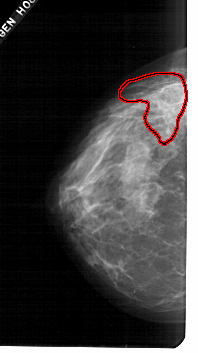

A_1698_1.LEFT_MLO

FILE: A_1698_1.LEFT_MLO.OVERLAY

TOTAL_ABNORMALITIES 1

ABNORMALITY 1

LESION_TYPE CALCIFICATION TYPE PLEOMORPHIC DISTRIBUTION SEGMENTAL

ASSESSMENT 5

SUBTLETY 4

PATHOLOGY MALIGNANT

TOTAL_OUTLINES 1

BOUNDARY